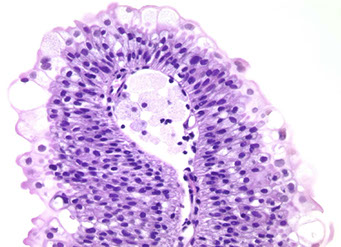

Inverted papilloma

Rare, b9 urothelial tumor, presents c hematuria and irritative sx

- 7M.1F, usually ~50 yo

- usually trigone and bladder neck

- b9 and not related to urothelial carcinoma

Micro: smooth surface covered by normal urothelium and endophytic growth of urothelial cells aroborizing extensively from surface urothelium to lamina propria

- anastomosing cord, columns and thin trabecula

- peripheral pallisading with spindly nuclei

- no atypia or mits

- no exophytic component

- may see squamous morules

- may show non-keratinizing squamous metaplasia

DDx: inverted urothelial carcinoma

Inverted Papilloma Comparison to Urothelial Carcinoma

• Lacks cytological atypia

• Mitotic activity limited to basal cell layer

• Lacks inflammation and reactive stroma

• Squamous metaplasia lacks keratin formation

• Lacks muscularis propria invasion

Px: recurrence ~1%